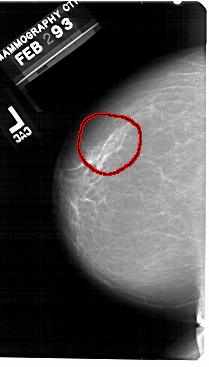

A_1493_1.RIGHT_MLO

RIGHT_MLO LINES 5491 PIXELS_PER_LINE 3556 BITS_PER_PIXEL 12 RESOLUTION 43.5 NON_OVERLAY

FILE: A_1493_1.LEFT_CC.OVERLAY

TOTAL_ABNORMALITIES 1

ABNORMALITY 1

LESION_TYPE CALCIFICATION TYPE PLEOMORPHIC DISTRIBUTION SEGMENTAL

ASSESSMENT 4

SUBTLETY 4

PATHOLOGY BENIGN

TOTAL_OUTLINES 1

BOUNDARY